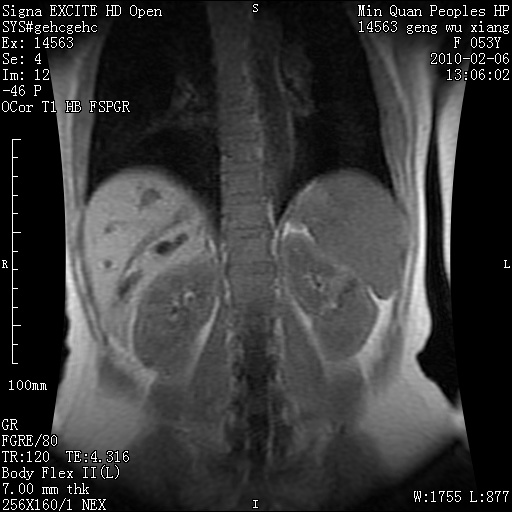

标题: MRI2762:胆道梗阻原因?

f,53y,全身黄染多日。

高位胆道梗阻 胆管癌可能性大

支持 高位胆道梗阻 胆管癌可能性大。